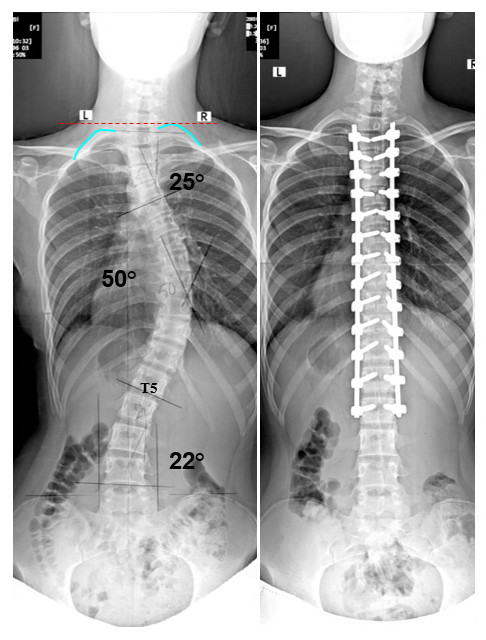

Skolyoz ve kifoz cerrahisinde riskler daha fazla ve çıkabilecek komplikasyonlar çok daha fazladır.Bu gelişebilecek erken veya geç

dönem komplikasyonlar bu cerrahinin uygulanması gerektiren tüm hastalarda gelişebileceği gibi bu cerrahiyi uygulayan tüm omurga

cerrahlarında da gelişebilir. Bundan dolayı hekiminizle kore olmanız uyum içinde aynı yönde hareket etmeniz önemlidir.

Omurga operasyonları

Omurgada kaymalar olabilir, omurgada kırıklar olabilir, omurgada eğrilikler kifoz veya skolyoz olabilir. İşte bu sorunlar derecelerine tespit

Omurga operasyonlarında amaç omurgadaki dizilimi sağlamak en azından ilerlemesini engellemektir.